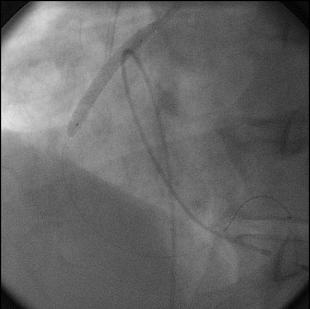

PTCA with stenting of mid RCA was done through right femoral approach with temporary pacemaker support. We faced great difficulty in engaging RCA due to anomalous high origin above left coronary sinus (Figure 5) resulting in kinking, coiling and distorted shaping of various guide catheters. We used 6Fr AR, AR2, AL2, JL3, XB3.5, JR, multipurpose Hockeystick II and RBV guide catheter but failed in getting adequate alignment (Figure 6,Figure 7). Finally, we succeeded using an AL1, 6Fr guide catheter. Mid RCA lesion was stented with AXXION (paclitaxel coated) 2.75mm x 18mm at 10 to 14atms pressure inflations (Figure 8). Post stent angiogram showed TIMI grade III flow without any complications (Figure 9, Figure 10).